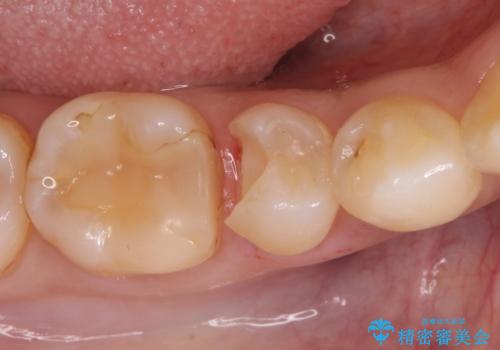

- 歯が欠けて、そこに食べ物が詰まるとのことで来院されました。

虫歯が大きく進行していました。

顕微鏡下で丁寧に虫歯を取り除き、セラミックインレーによる修復治療を行いました。